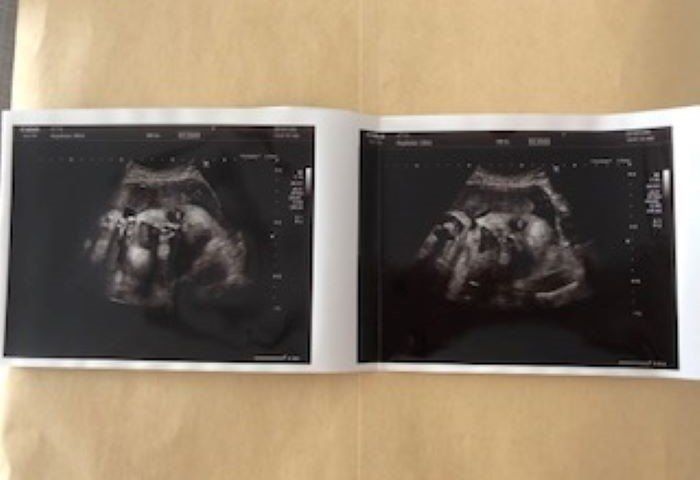

妊娠28週 どことなく長男に似ている…

28w5d 1238g

妊婦28週目。いよいよ妊娠後期に突入しました。赤ちゃんの推定体重は1238g。両手を顔の近くまで持ってくるポーズが、赤ちゃんのお気に入りのようでした。画像越しに見る赤ちゃんは、いつもこのポーズで写っていました。頭の形や横顔、顔の輪郭がどことなく長男に似ているように、私には見えました。